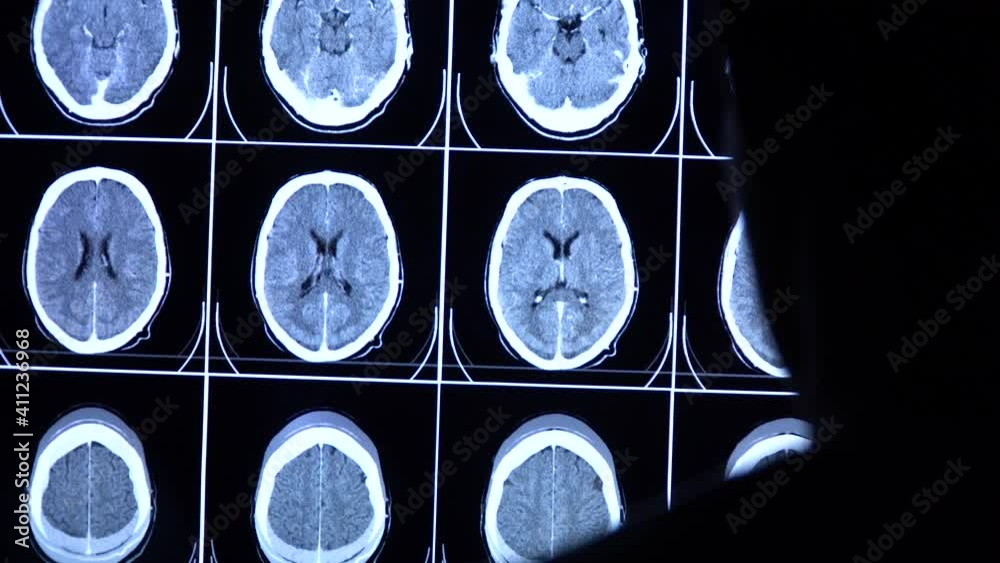

CT Scan of Brain fliming''SIEMENS'' YouTube How To Check Your Brain Scan Mri is a type of scan that uses strong magnetic fields and radio waves to produce detailed images of the inside of the body. The test accurately details the size, shape, and function of the brain. Magnetic resonance imaging (mri) of the head is a painless, noninvasive test that produces detailed images of your brain and brain stem. Diagnostic brain. How To Check Your Brain Scan.

CT Brain Perfusion or CT scan image of the brain axial view showing How To Check Your Brain Scan Learn more about ct scans and how to be prepared. Computed tomography (ct) and magnetic resonance imaging (mri) have revolutionized the study of the brain by allowing. An mri machine creates the images. Diagnostic brain imaging tests can assess bone fractures, structural problems, blood vessel abnormalities, and changes in brain metabolism. Ct scans of the brain can provide detailed information. How To Check Your Brain Scan.

MRI brain scans axial view offer valuable insights into brain anatomy How To Check Your Brain Scan Magnetic resonance imaging (mri) of the head is a painless, noninvasive test that produces detailed images of your brain and brain stem. An mri machine creates the images. Diagnostic brain imaging tests can assess bone fractures, structural problems, blood vessel abnormalities, and changes in brain metabolism. Ct scans of the brain can provide detailed information about brain tissue and brain. How To Check Your Brain Scan.

Medical scientist scrolls CT, MRI brain scan images on a big screen How To Check Your Brain Scan Ct scans of the brain can provide detailed information about brain tissue and brain structures. Computed tomography (ct) and magnetic resonance imaging (mri) have revolutionized the study of the brain by allowing. An mri machine creates the images. The test accurately details the size, shape, and function of the brain. Learn more about ct scans and how to be prepared.. How To Check Your Brain Scan.